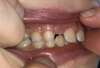

1)      Photo de face : Placer l’index et le majeur de chaque main dans le coin de la bouche, légèrement écartés et tirer vers l’extérieur pour bien dégager les zones postérieures.

Placer l’appareil photo (ou le portable) bien en face des dents, zoomez si nécessaire, avec le flash de préférence.

Faites une photo dents serrées et une photo dents légèrement entrouvertes.

2)      Photos de côté : laisser les doigts en bouche et tirer d’un côté sur le coin de la bouche vers l’oreille, les doigts du côté opposé ne tirent pas mais écartent légèrement les lèvres sur l’avant.

Prendre la photo en se plaçant bien sur le côté, perpendiculairement aux dents (dents serrées – croquer sur les molaires)

Recommencer de l’autre côté.